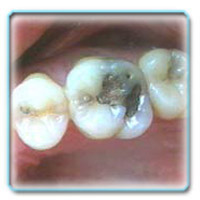

Термин кариес зубов в точном переводе означает гниение. Говоря же научным языком, кариес — патологический процесс, проявляющийся деминерализацией и последующим разрушением твердых тканей зуба под воздействием кариесогенной микрофлоры с образованием дефекта в виде полости.

Проще говоря, кариес — это разрушение зуба, которое начинается с растворения минеральных веществ, входящих в состав зуба, и с последующими образованием дырки. Размывание минеральных веществ, образующих эмаль, происходит под воздействием деятельности микробов. «Переваривая» углеводы, бактерии выделяют органические кислоты, которые, в свою очередь, приводят к возникновению кислой среды во рту.

Все это способствует разрушению кристаллов апатита, входящего в состав эмали. После этого микробы проникают в нижележащие слои и начинают разрушать их.

Лечение кариеса проводится с обязательной механической обработкой кариозной полости при помощи бора. После обработки полость получается немного больше кариозной, но при этом достигается главная цель – полное удаление дефектных участков, которые в дальнейшем могут способствовать повторному развитию кариеса. Затем проводится медикаментозная обработка полости и заполнение ее пломбировочным материалом.